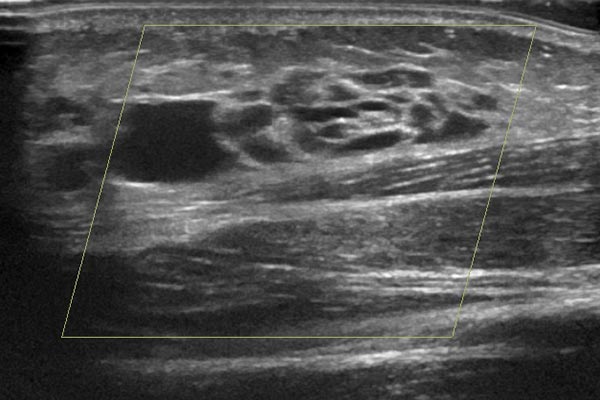

Zum gleichen Zeitpunkt, farbkodierte Duplexsonographie der Läsion. Es handelt sich klar um eine Slow-flow-Läsion mit niedrigem Durchfluss, keine Farbsignale innerhalb der Läsion. Aufgebaut ist sie aus echoarmen, zystisch erscheinenden Räumen mit dünner Wandung und echofreiem Inhalt.

Die Biopsie erfolgte in gleicher Sitzung ultraschallgesteuert mit einer Einmalbiopsiepistole. Die Biopsienadel wird mit einem Federsystem ca. 2 cm in das Gewebe „geschossen“ und über eine kleine Einbuchtung in der Nadel ein kleiner Gewebezylinder von wenigen Millimetern Dicke und knapp 2 Zentimeter Länge gewonnen. Wenn der Zielort dieser sehr kleinen Gewebeprobe gut gewählt wurde, ist hier eine histopathologische Beurteilung sehr gut möglich ohne größere Verletzung.